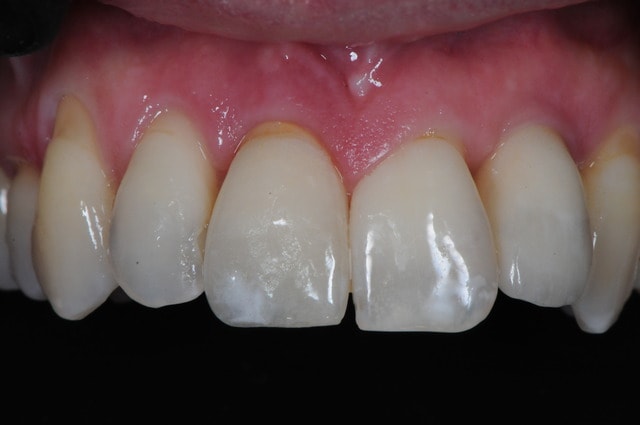

Dsc 0964 qivimn - Eugenol

Bourdon scan avant qxy44n - Eugenol

Le problème de faire comme ça c'est que tu positionnes ton implant au hasard. Tu fais une estimation de la position verticale de ton rebord osseux après cicatrisation.

Un coup ça marche, un coup ça marche pas. Tu peux très bien te retrouver avec un feston gingival absolument hideux.

La photo #4 montre l'implant en position finale ?

beau travail, mais

les 2 cas ne me semblent pas comparable dans la mesure ou tu as réussi à préserver un bandeau d'os vestibulaire presque au niveau des collets. Il permet un effet piquet de tente incomparable et évite les mauvaises surprises de perte importante de volume de biomat a la cicatrisation.

Dans l'autre cas la table vestibulaire est manquante, le résultat d'une EII beaucoup moins prévisible et dans un secteur esthétique j'aime pas jouer a la roulette russe.

Oui, l'implant est en position finale sur la photo 4.